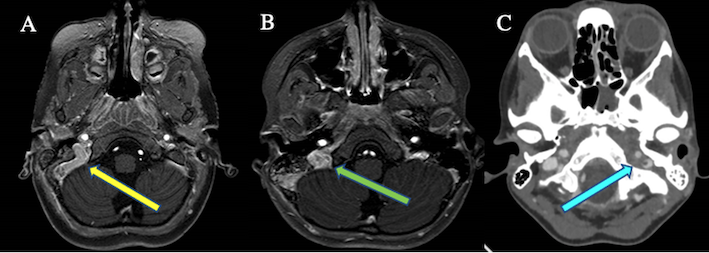

La TC e l’angio-TC eseguite in urgenza hanno rivelato in tutti i pazienti otomastoidite con trombosi del seno sigmoideo omolaterale, con coinvolgimento del seno cavernoso in un caso (Figura 1A, B e C).